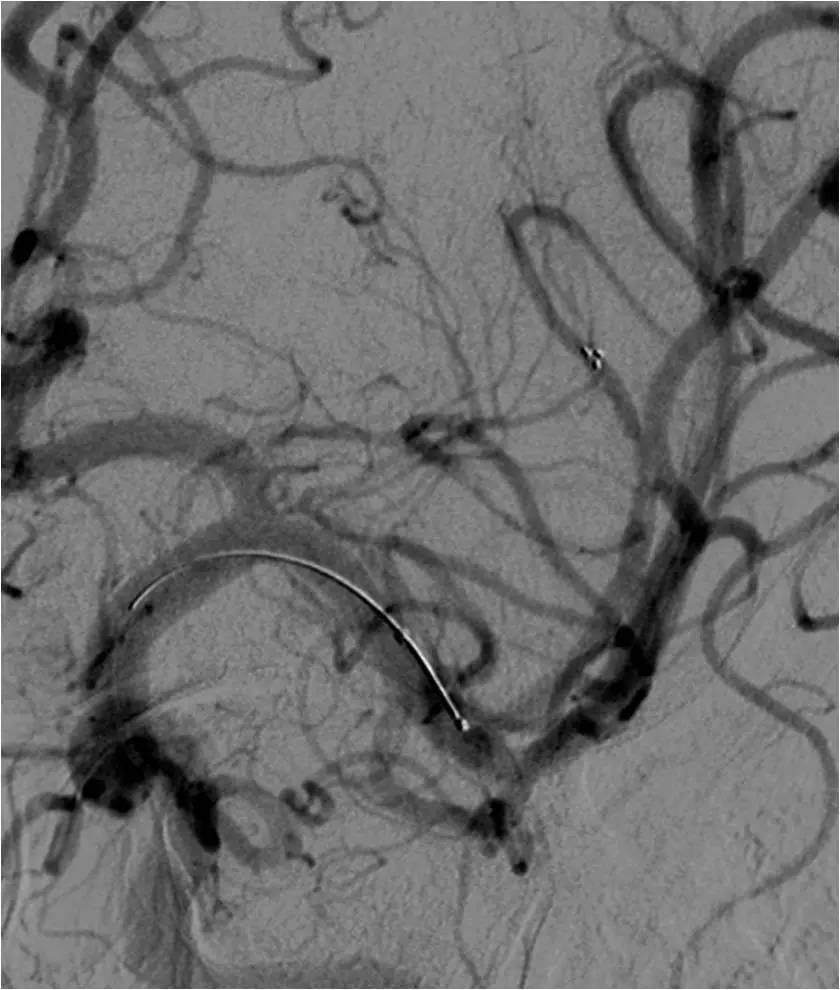

》全麻下手术

》术后C臂CT无出血

》术后20小时复查头颅CT无出血。